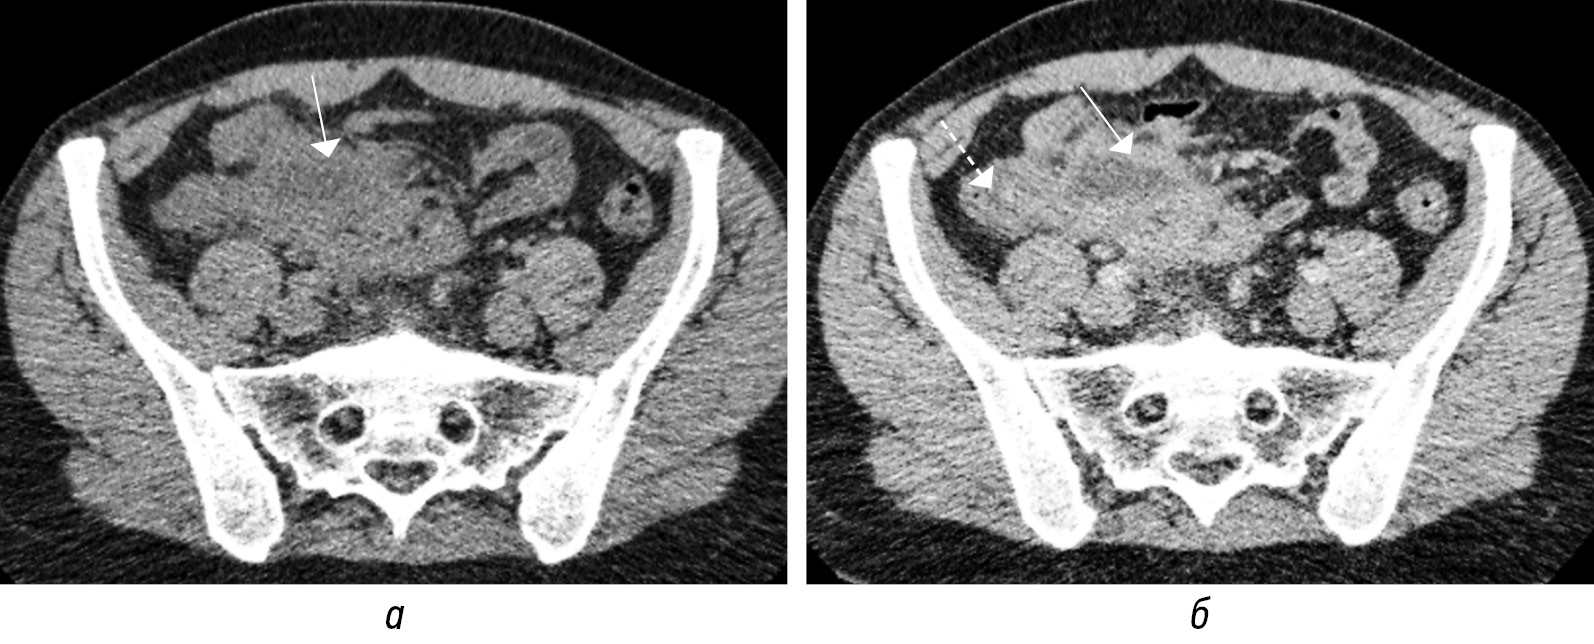

Отдельные авторы рекомендуют использовать пороговый диаметр 9,25 мм, опираясь на проведенный анализ литературы и обосновывая это тем, что диаметр нормального аппендикса может составлять более 6 мм [14]. В 2015 г. Trout A.T. et al. сообщили о более высокой точности трехкатегориальной интерпретации диаметра аппендикса при УЗИ в диагностике ОА у детей, чем традиционное пороговое значение 6 мм [23]. По их данным, ОА присутствовал в 2,6, 65 и 96 % соответственно при диаметрах аппендикса до 6 мм, от 6 до 8 и свыше 8 мм. Авторы статьи считают, что диагноз ОА не следует ставить только на основании диаметра, поскольку это приведет к ложноположительным результатам (рис. 5, а, б) [23].

Рис. 5. КТ-изображения во фронтальной плоскости в нативную фазу (а, б) нормального аппендикулярного отростка с диаметром 8,09 мм и содержащим пузырьки газа (стрелки) без клинических признаков острого аппендицита

Fig. 5. CT images in the frontal plane in the native phase (а, б) of a normal appendicular process with a diameter of 8,09 mm and containing gas bubbles (arrows) without clinical signs of acute appendicitis